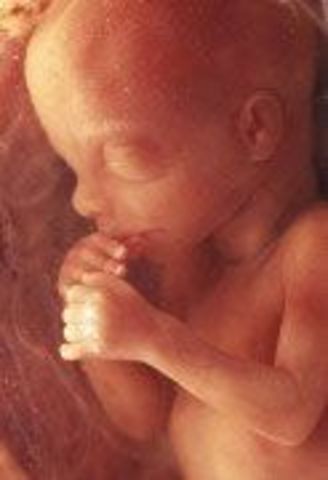

• Week 23

Week 23

Fetus can suck thumb with no problem. Inner ear helps with controling balance. Pancreas developes.